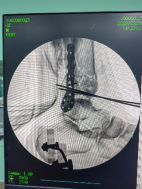

控制機器人牽引斷端,可見關(guān)節(jié)間隙恢復。

外側(cè)切口放置鋼板,固定腓骨。

穿針輔助復位脛骨遠端骨折塊,安裝內(nèi)固定